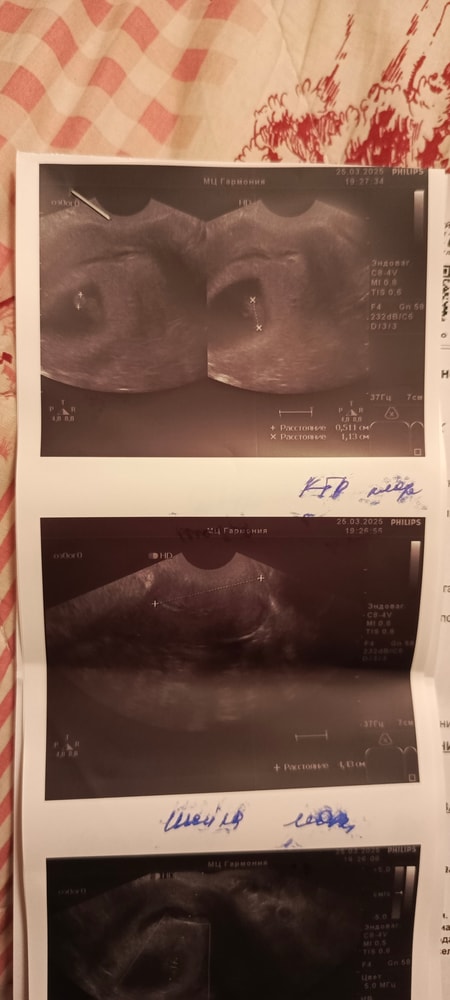

Вторая полость в матке. Двурогая матка?

Ну, вижу перегородку тоже Попробуйте переделать УЗИ у еще специалиста, моей маме сказали про двурогость когда она забеременела только младшей сестрой моей, а у меня еще старшая и я)) у меня двурогость, обратили сразу при первом обследовании

Lisa, не переживайте, снимки не четкие, одна полость, одно плодное яйцо. Перегородка она при двурогой матке есть У вас нет, сравнила свои снимки, у вас не так

Alenchik, прикрепила в исходное сообщение фото узи

Наше узи Размер плода 16+5